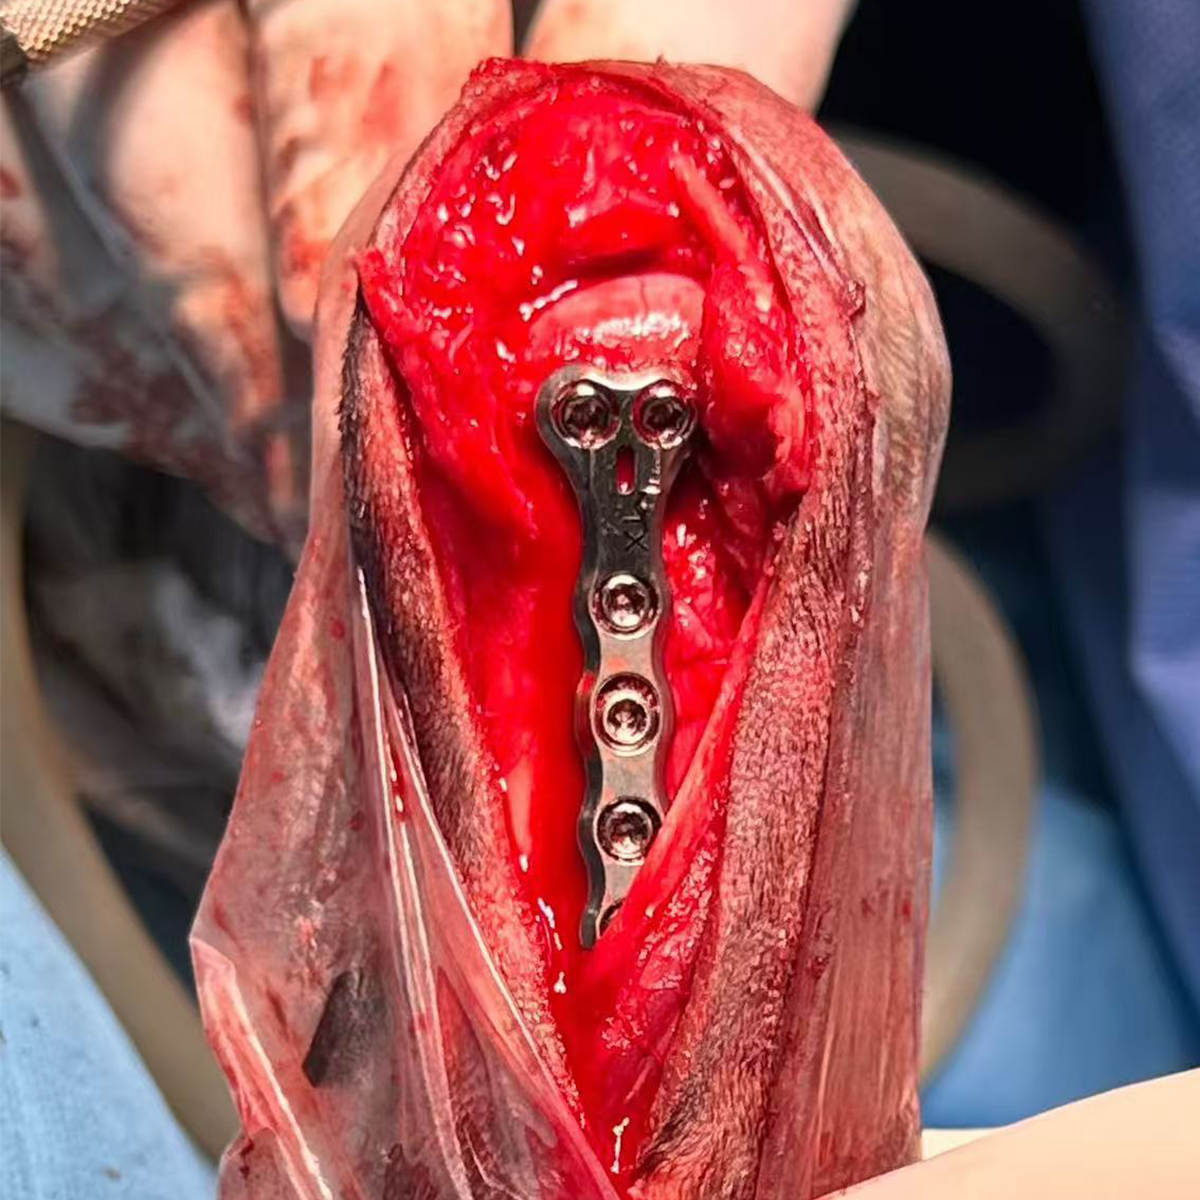

2.4/2.7mm Hybrid Polyaxial T Locking Plate

Length 48mm Partial Carpal Athrodesis